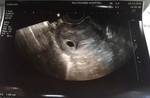

สามีเเพ้ท้องเเทน

จะหายเมื่อไหร่คะ ตอนเเรกเราเเพ้หนักมากจนเข้าโรงพยาบาล พอเราดีขึ้นสามีกับเป็นหนักขึ้น อ้วกตลอด กินอะไรไม่ได้ เวียนหัวทำงานไม่ได้เลย มีทางช่วยบรรเทาอาการบ้างมั้ยคะ